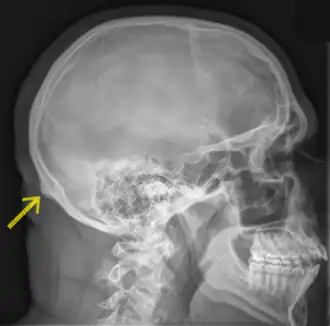

![]() Radiografía de un cráneo humano en vista lateral. Inion indicada por la flecha amarilla. | ||

El inion es la proyección más prominente del hueso occipital en la parte posterioinferior del cráneo humano. El ligamento nucal y el músculo trapecio se insertan a este nivel.

El término protuberancia occipital externa (protuberantia occipitalis externa) se utiliza a veces como sinónimo, pero con mayor precisión el término "inion" se refiere al punto más alto de la protuberancia occipital externa.

El inion se utiliza como un punto de referencia en el sistema de 10 a 20 en la grabación de electroencefalograma (EEG).